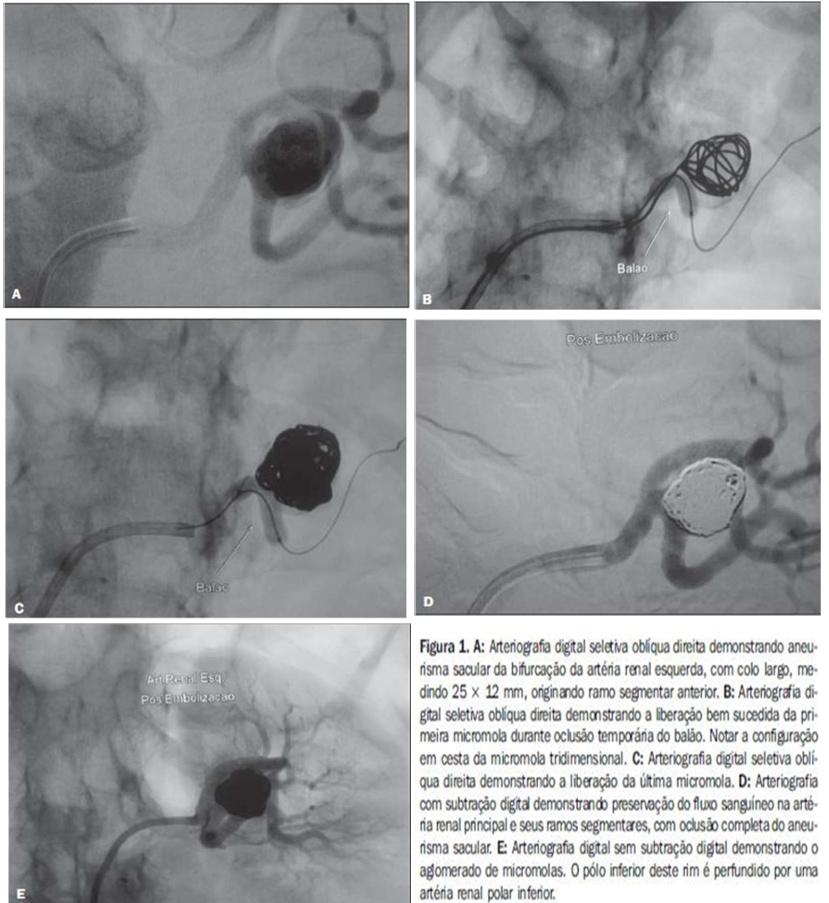

Caso realizado pelo serviço HCI da Santa Casa de Ribeirão Preto, evidenciando um grande aneurisma na artéria renal esquerda que foi tratado com técnica endovascular sendo utilizado coils e stent ATLAS. Caso da literatura de aneurisma de artéria renal evidenciando técnica de remodelagem de tronco com insuflação de balão no colo do aneurisma.